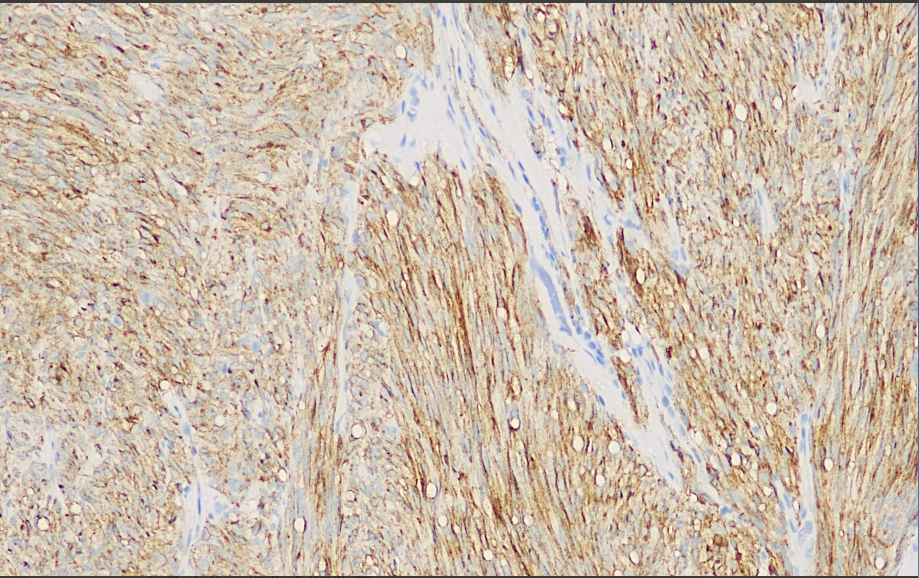

Positive control: Gastrointestinal mesenchymal tumor

PDGFRa is one of the important markers of GIST, and PDGFRa gene mutation is present in about 5% - 10% of GIST with high protein expression. Immunohistochemical detection of PDGFRa can help in the diagnosis of GIST, especially for CD117-negative GIST cases, and the detection of PDGFRa can improve the diagnostic accuracy. Some soft tissue tumors, such as fibromatosis and bulging cutaneous fibrosarcoma, may be morphologically similar to GIST. the expression of PDGFRa in these tumors is different from that of GIST, and the detection of PDGFRa by immunohistochemistry in conjunction with other markers can help in differential diagnosis and avoid misdiagnosis.

PDGFRα antibody reagents can specifically bind to PDGFRα molecular antigens. Immunohistochemistry kits containing PDGFRα antibody reagents are suitable for the auxiliary diagnosis of gastrointestinal stromal tumors (GIST) and certain sarcomas (such as fibrosarcoma).